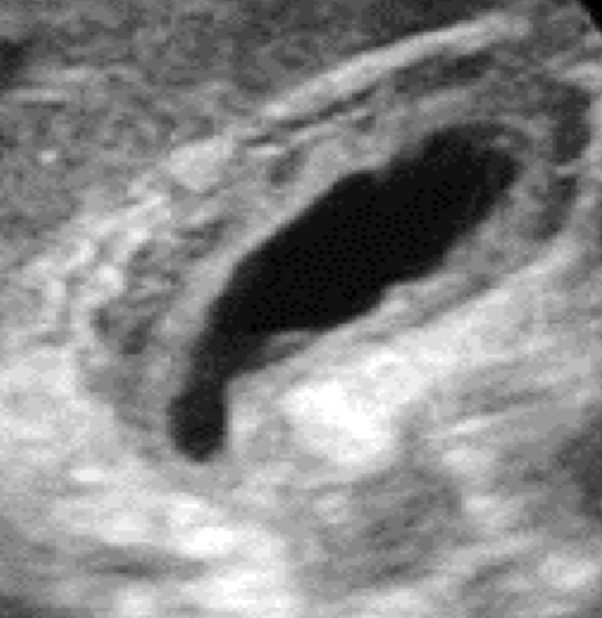

chronic cholecystitis

recurrent attacks of acute cholecystitis with fibrosis of GB wall

s/s: neg. Murphy’s; RUQ pain but no tenderness

SONO:

neg. Murphy’s sign

contraction of GB

stones

WES sign